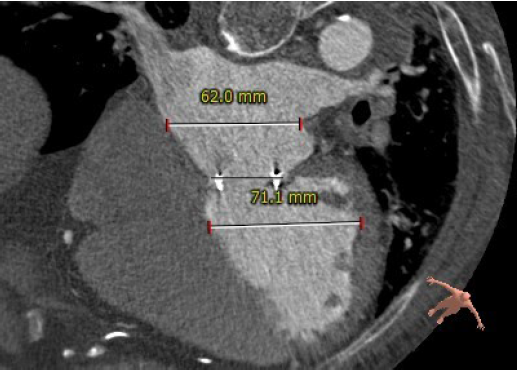

左房及左室内径